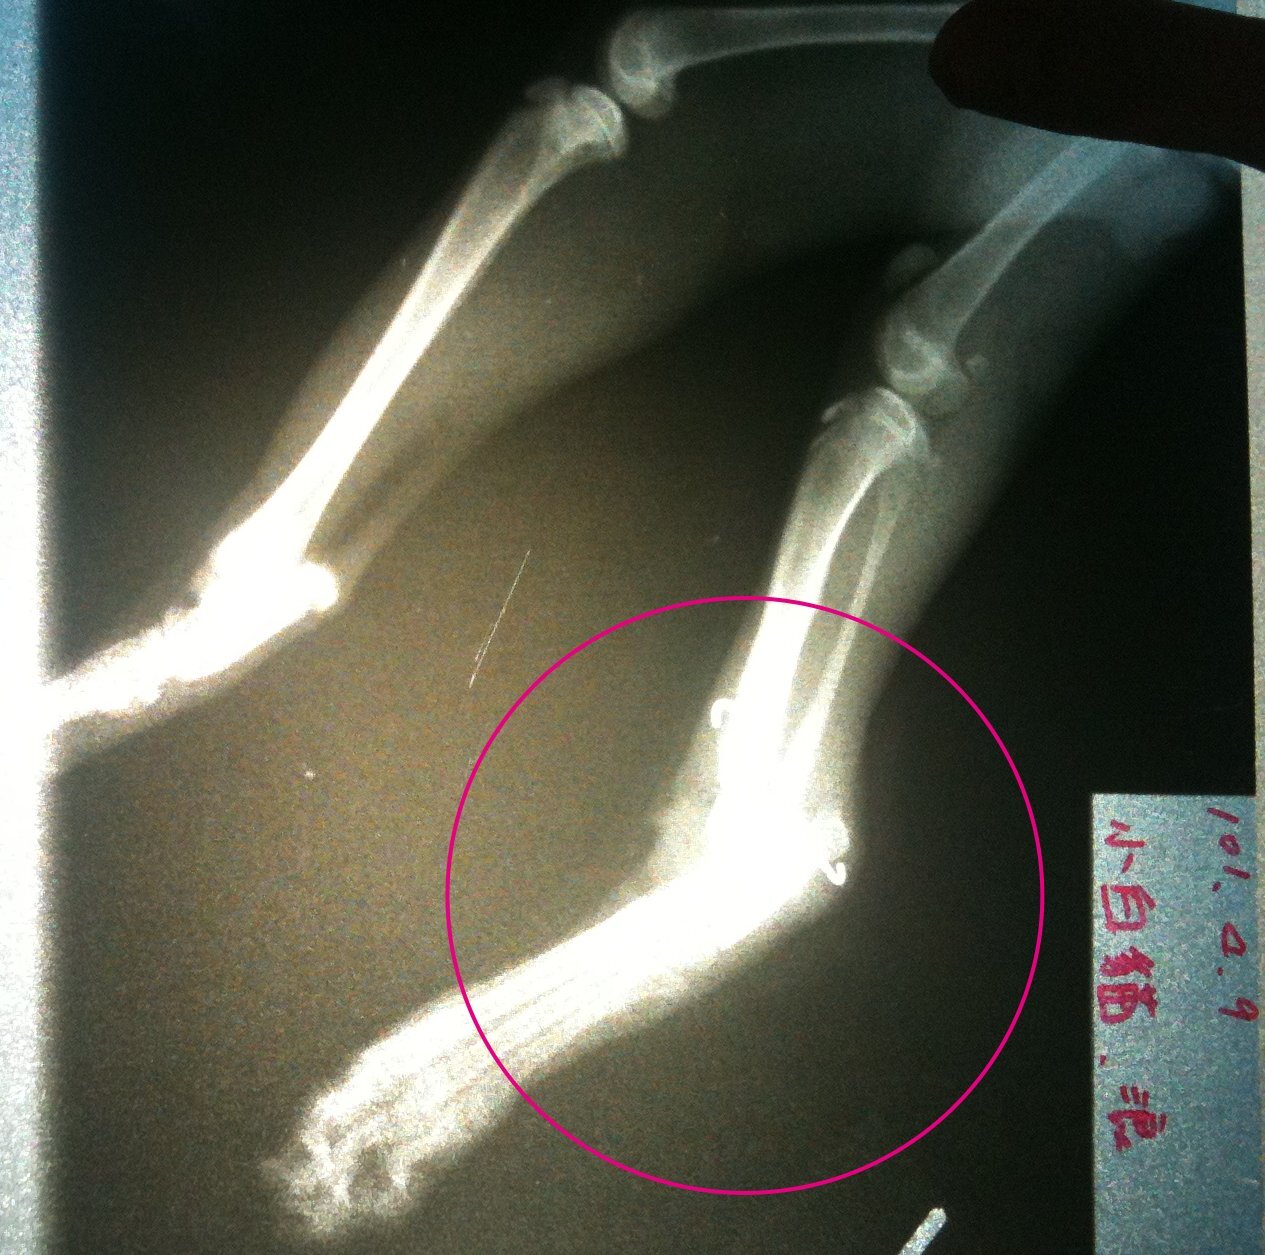

經由X光片可看到右前肢肩頰骨處、右後腿的關節蓋已於第一次手術中被切除,

並用鐵絲固定,

看得出手術不成功,

也造成後腿腫脹與嚴重感染。